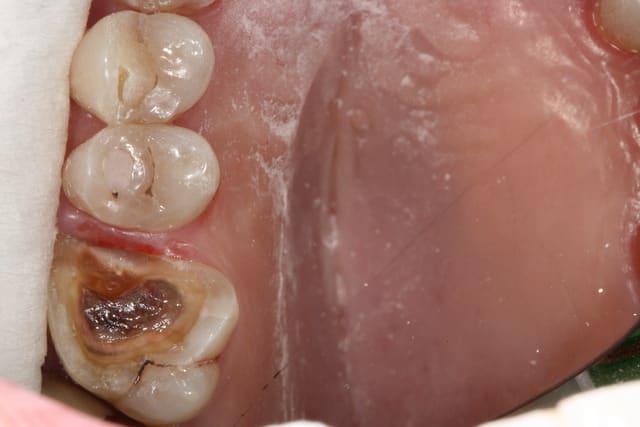

Photo 1. Moi: "Voilà pourquoi il vous faut un onlay."

Photo 3. Le patient: "Ah quand même! Ben on va faire les autres alors!"